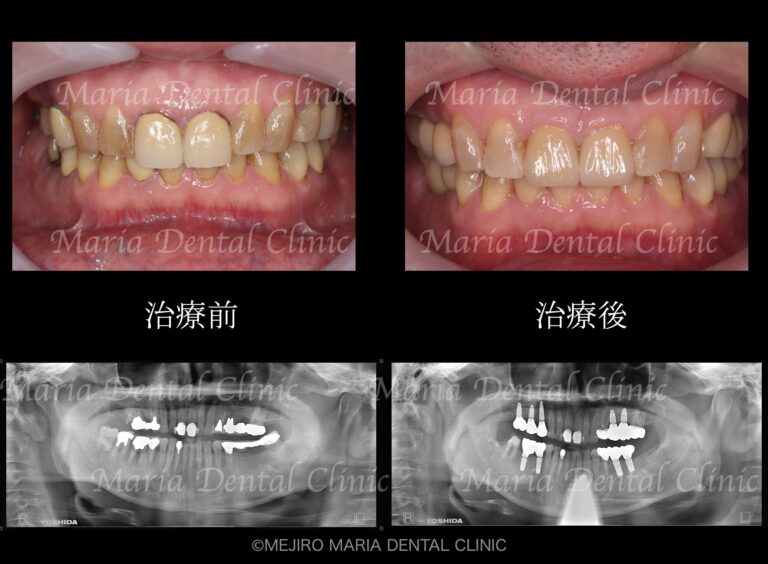

• 目白マリア歯科【症例】チーム医療で行った全顎的な治療:精密根管治療による歯の保存と咬合崩壊を防ぐインプラント治療|治療前後の歯の比較画像_メイン2-1

【症例】チーム医療で行った全顎的な治療:精密根管治療による歯の保存と咬合崩壊を防ぐインプラント治療